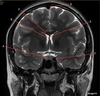

A

Genu Corpus Callosum

B

Splenium Corpus Callosum

C

Pons

D

Cerebellum

Image weighting and axis

T2 Flair

Sagittal